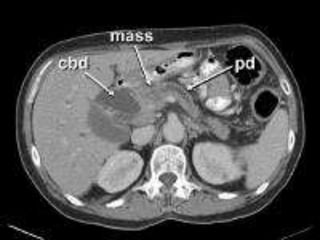

CT

 “Pancreatic protocol CT” is the gold

standard of investigation to stage the

disease and assess the operability

 Triple phase CT

 Closer cuts

 Water used as an intraluminal contrast

 Helical or multislice

 Focal or diffuse mass lesion which is hypo

dense (low attenuation) and hypo vascular

(poor contrast enhancement)

 Dilated MPD and CBD